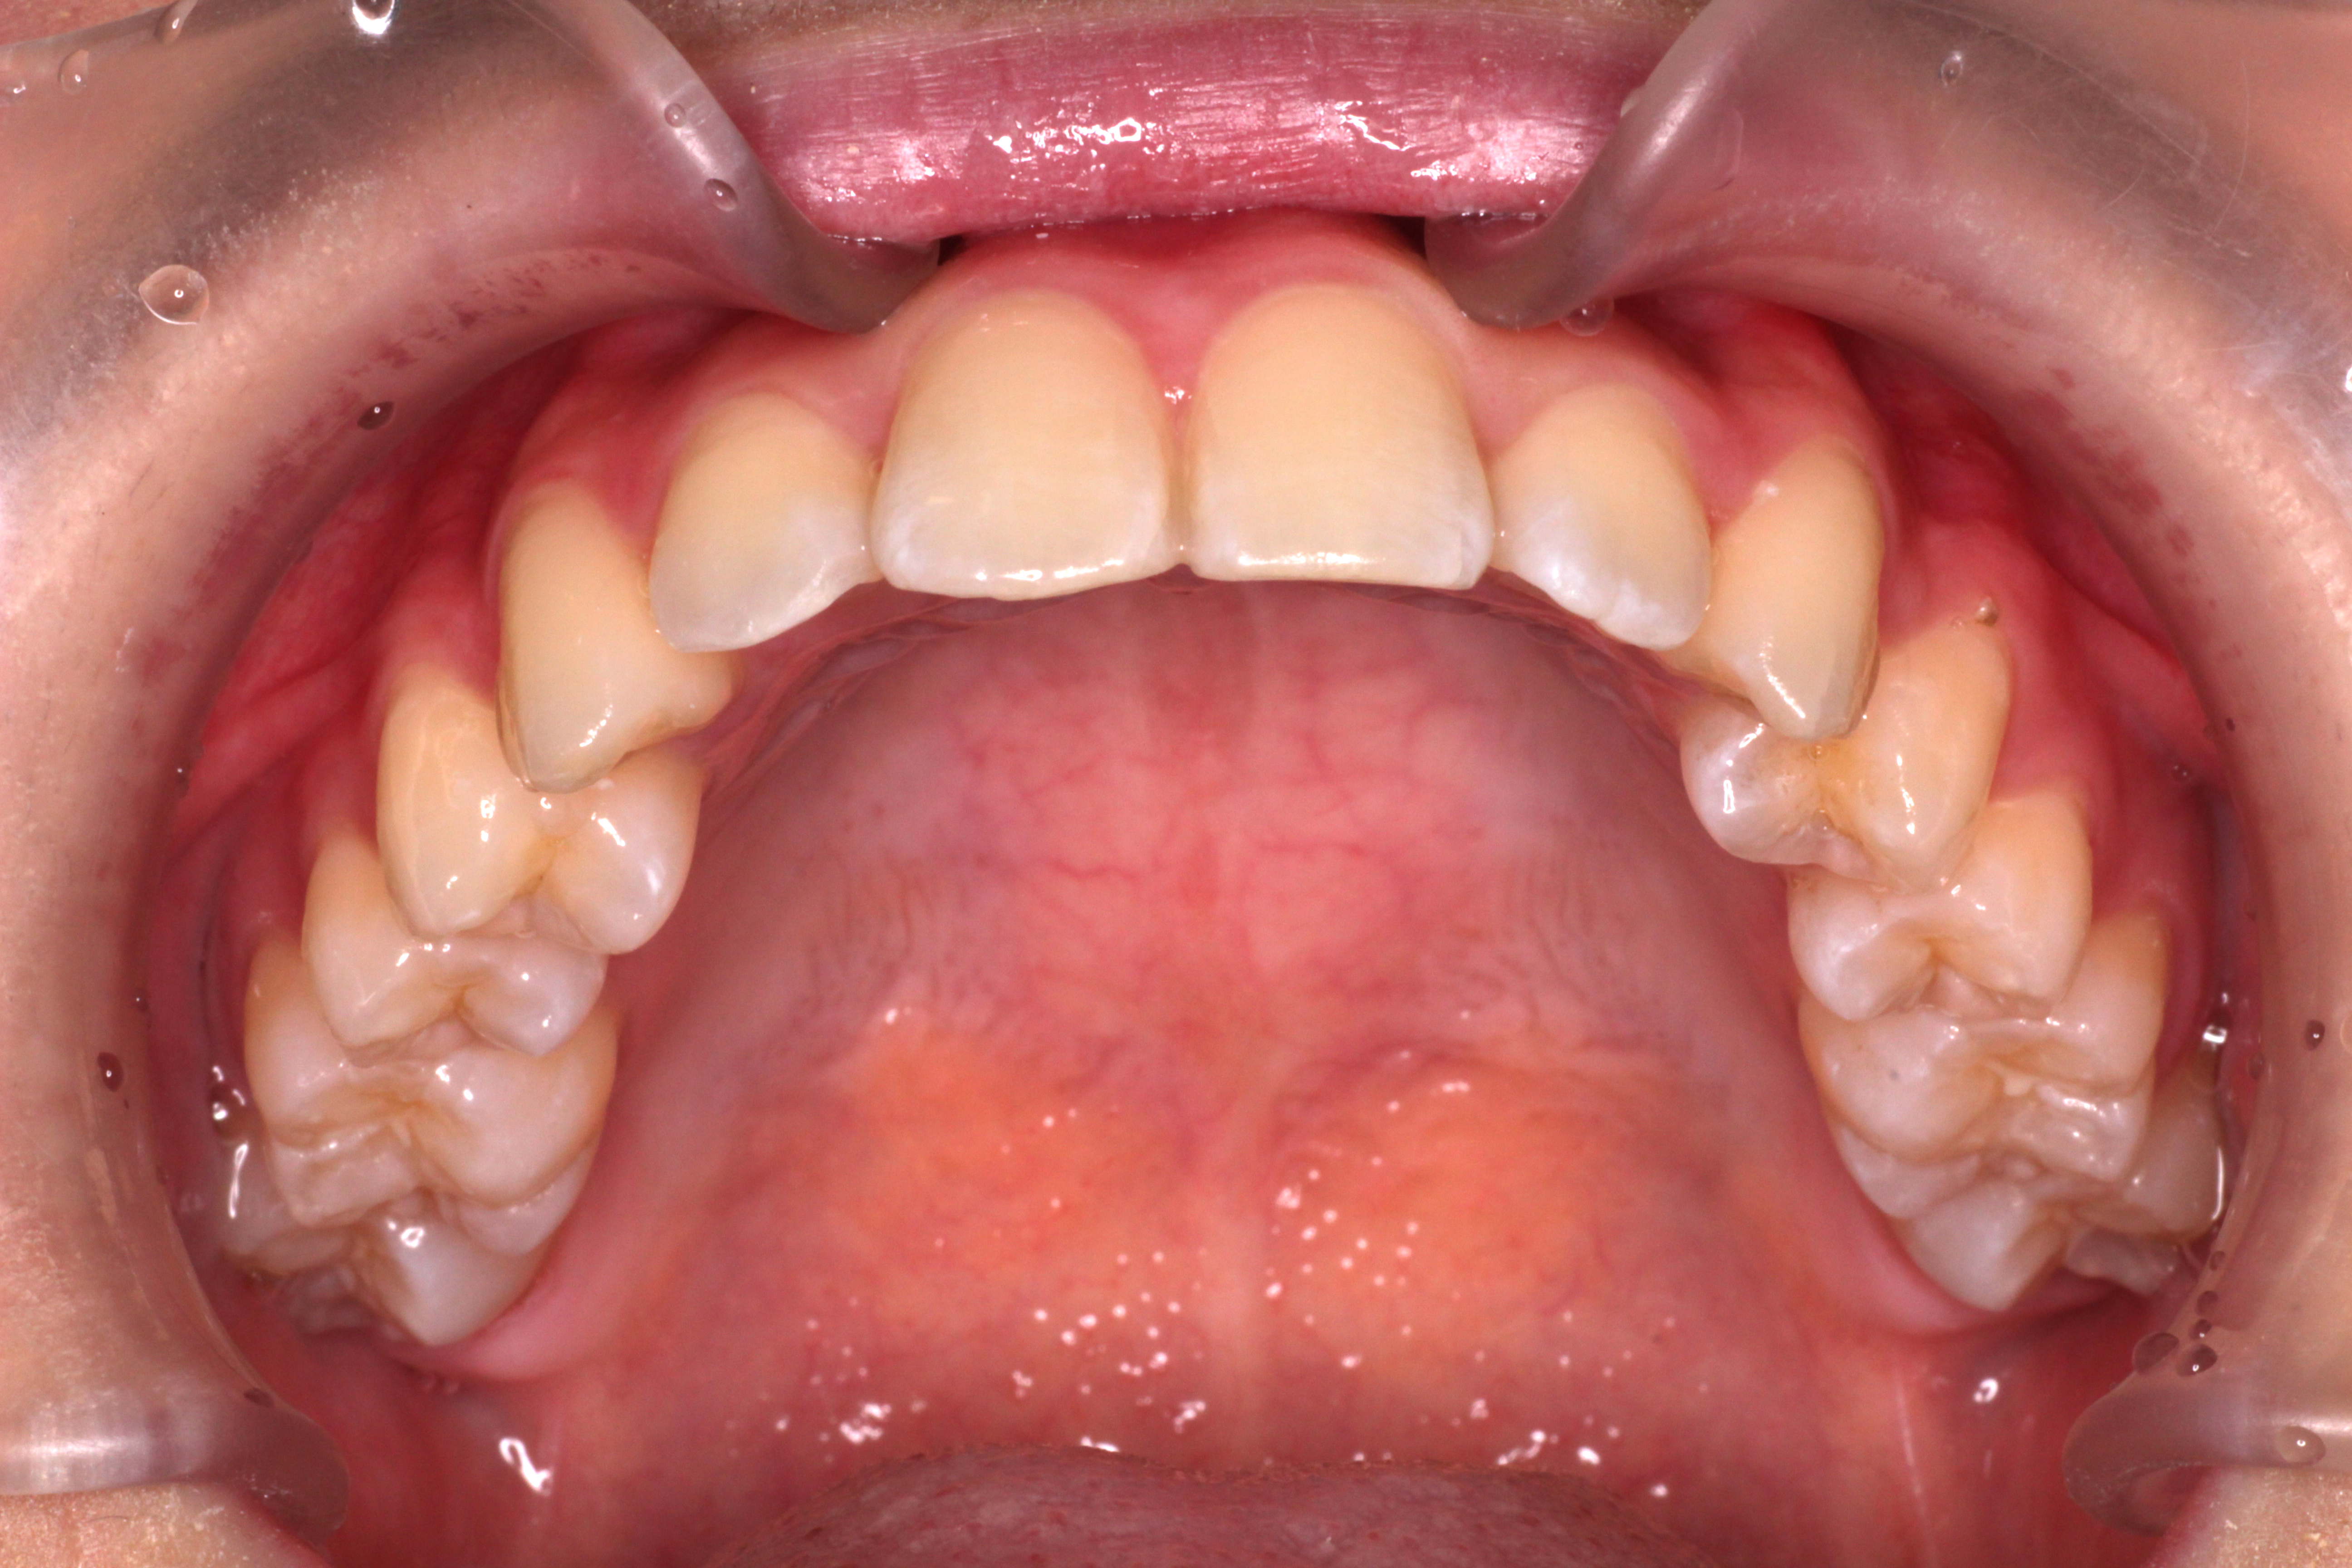

↓お口の中の状態です。

初診時からの変化と治すべきところは

⑴咬み合わせは下の歯が上の歯に隠れていましたが、見えるようになりました。

⑵右下の2番目の歯が歯列の中に納まってきましたが、まだ少しずれています。

⑶右上の2番目の歯は下の歯より前に出ましたが、咬み合わせが浅いです。

ここで新たな問題点が見つかりました。

⑷正中がずれているので、合わせるためにゴムかけをします。

⑴~⑷を改善するためにリファイメントを行います。